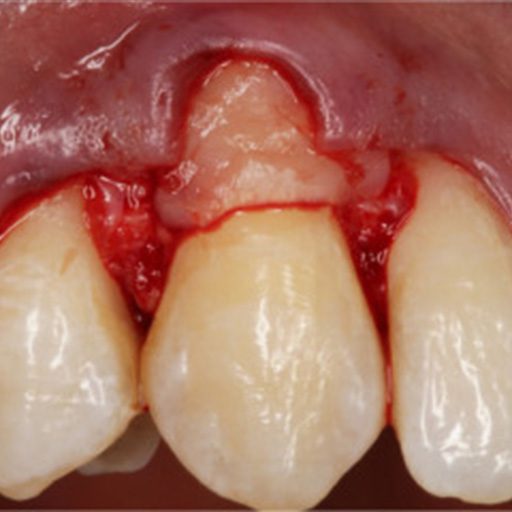

Tooth Preservation